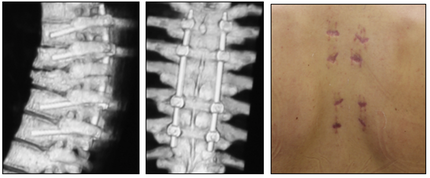

Таким образом, малоинвазивная ТПФ может быть рекомендована не только для стабилизации, но и для коррекции посттравматической деформации при нестабильных повреждениях. Так же малоинвазивный метод ТПФ следует предпочесть открытым методикам при реконструкции передней колонны позвоночника, в том числе при этапном хирургическом лечении (Рис. 2-5).

Рис. 4. Фиксация нескольких повреждённых сегментов позвоночника с реконструкцией передней колонны.

Рис. 5. Редукция, перкутанная ТПФ и моносегментарный межтеловой спондилодез при травматическом спондилолистезе L-V позвонка.